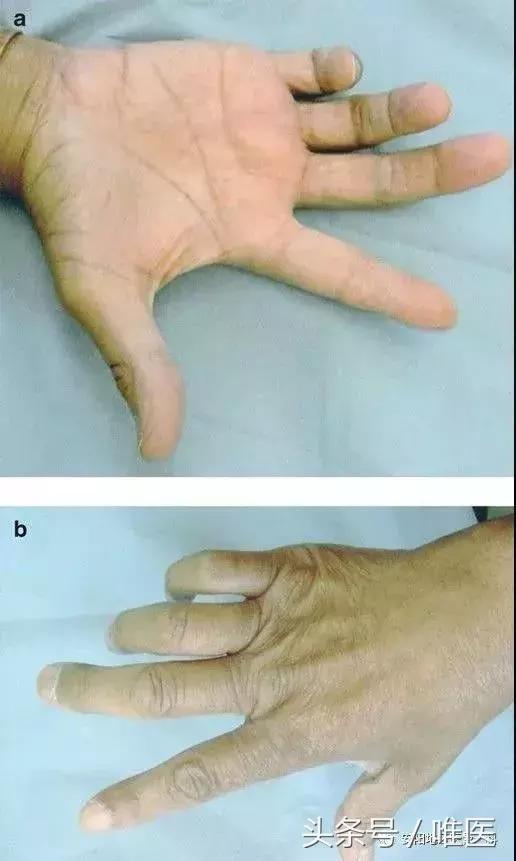

嚴重者出現手部尺神經支配區域的運動功能障礙、感覺喪失,典型表現是爪形手畸形,因手部小肌肉萎縮而手掌凹陷,掌指關節過伸,指間關節屈曲,因食指、中指的蚓狀肌受正中神經支配,故手指屈曲畸形以環指、小指為著,拇指常處於外展狀態,手指分開、合並動作受限制,小指動作喪失。感覺喪失區主要在手背尺側,小魚際、小指和無名指的尺側一半。

1、爪形手畸形、“虎口”處及各掌骨骨間肌萎縮、手部尺側麻木。

3、夾紙試驗(Froment征)陽性:囑患者用患側食指與拇指捏夾一張紙,患側因拇內收肌癱瘓,無法完成此動作,而用指間關節屈曲代償,為典型的Froment征陽性,尺神經癱瘓。